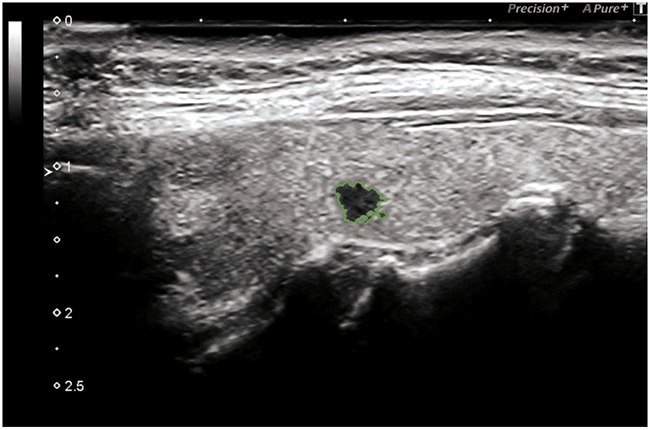

Bidimensional ultrasonography (DUS 2) using high frequency probes (13 - 15 MHz) (Toshiba Aplio 500) highlighted a highly suspicious micro-focus of the left lobe, of radial shape with markedly hypoechoic echostructure, irregular margins, size 0.3 cm (classified TI-RADS 5, very high risk lesion ATA guidelines).

Figure 1: Hypoecogenic micro-focus, irregular margins.

The micro-focus identified was localized at the middle third of the left lobe, presenting a radial shape, markedly hypoechoic echostructure, irregular margins, size 0.3 cm, characteristics with a high predictive for malignancy value (p <0.001) [19].